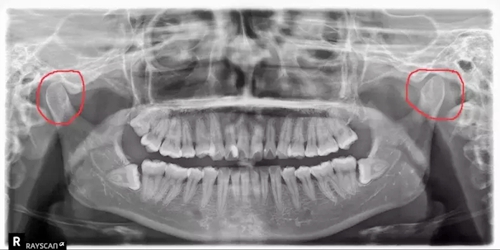

牙科醫(yī)生在看患者的X光片的時(shí)候,經(jīng)常能看出來(lái)有的人有偏側(cè)咀嚼的習(xí)慣,導(dǎo)致關(guān)節(jié)一側(cè)大一側(cè)小。

(如下圖:)